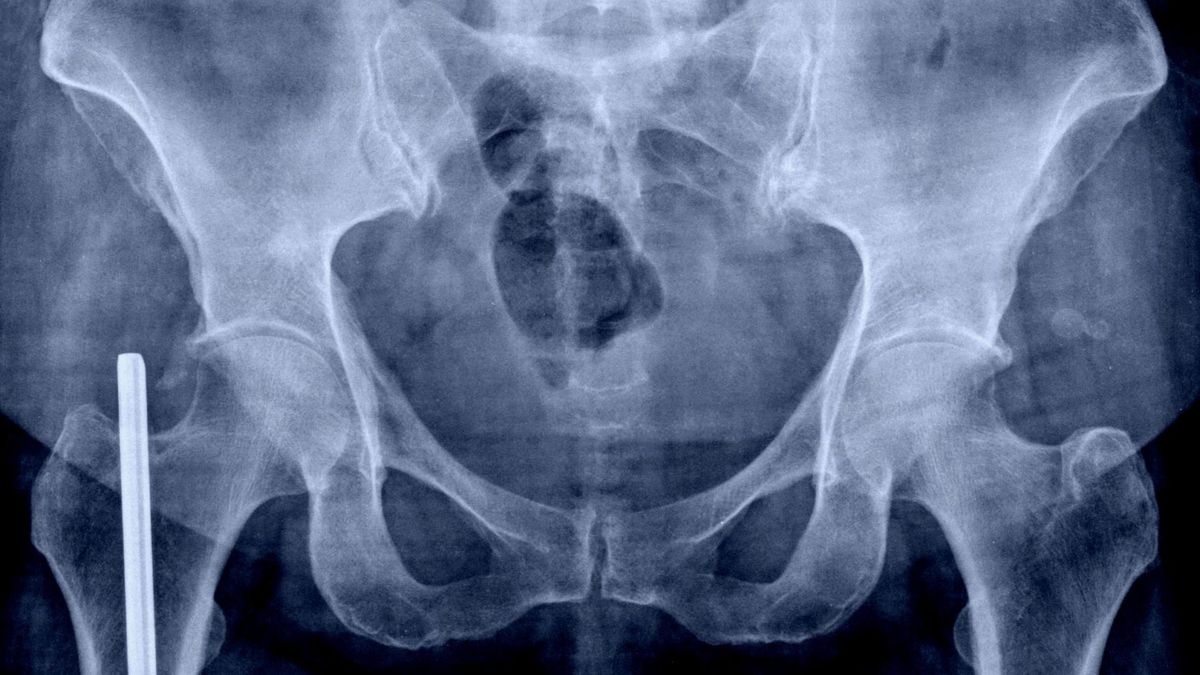

Wegetarianie mają większe ryzyko złamań biodra niż osoby jedzące mięsoWegetarianie mają większe ryzyko złamań biodra niż osoby jedzące mięso

Wpływ niejedzenia mięsa na zdrowie kości wzięli pod lupę naukowcy z Uniwersytetu Oksfordzkiego. Okazało się, że wegetarianie i weganie wykazują większe tendencje do złamań kości, np. biodra.

Naukowcy przyjrzeli się ryzyku dość rzadkich wypadków – złamań biodra. Okazało się, że u wegan to ryzyko było na poziomie 2,3 razy większy niż u osób jedzących mięso. Z kolei u wegetarian i osób, które jadły ryby – ryzyko było 25 proc. większe.